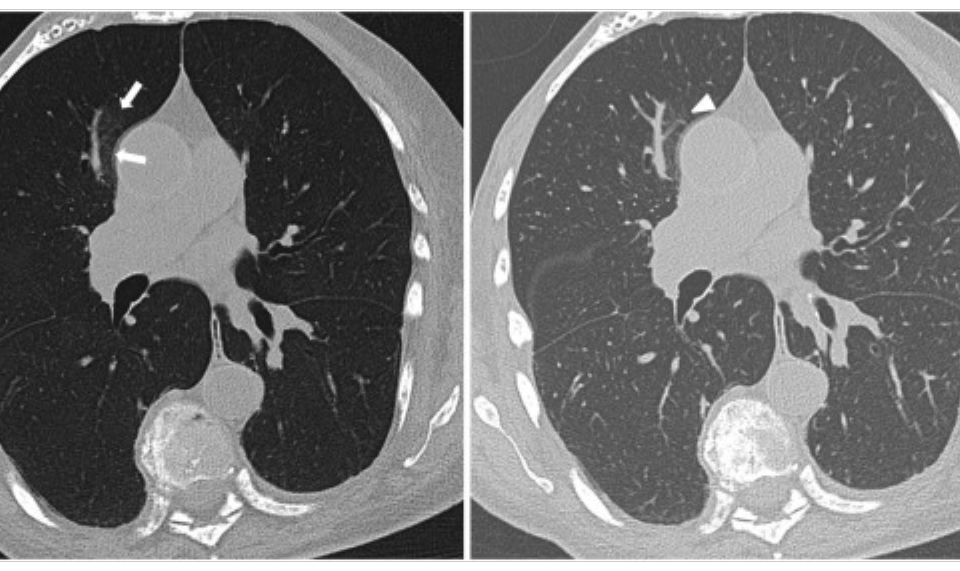

Minimum Intensity Projection (MinIP)

Her açıdan en düşük dansite değerine sahip voksellerin birleştirilerek iki boyutlu görüntüye aktarılması ile oluşturulur. Sarus PACS MinIP aracı ile sadece hava dansitesine eşit ya da […]